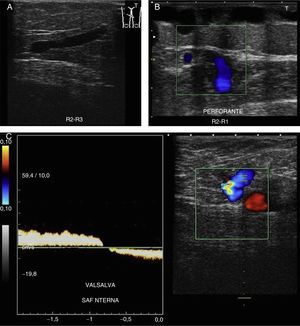

Valsalva: aumentando la presión toracoabdominal2,10,11,18 (fig. 8A).

Compresión/relajación distal2,6,10,12: realizar compresión distal hasta que desaparezca el flujo; se considera positivo el reflujo cuando al cesar la compresión se detecta flujo invertido, que se manifiesta como cambio de color e inversión de la curva espectral19,20, en cortes transversales y con Doppler color.

Comenzaremos el estudio a nivel de la unión safenofemoral en modo B (signo de Mickey Mouse) (fig. 8B).